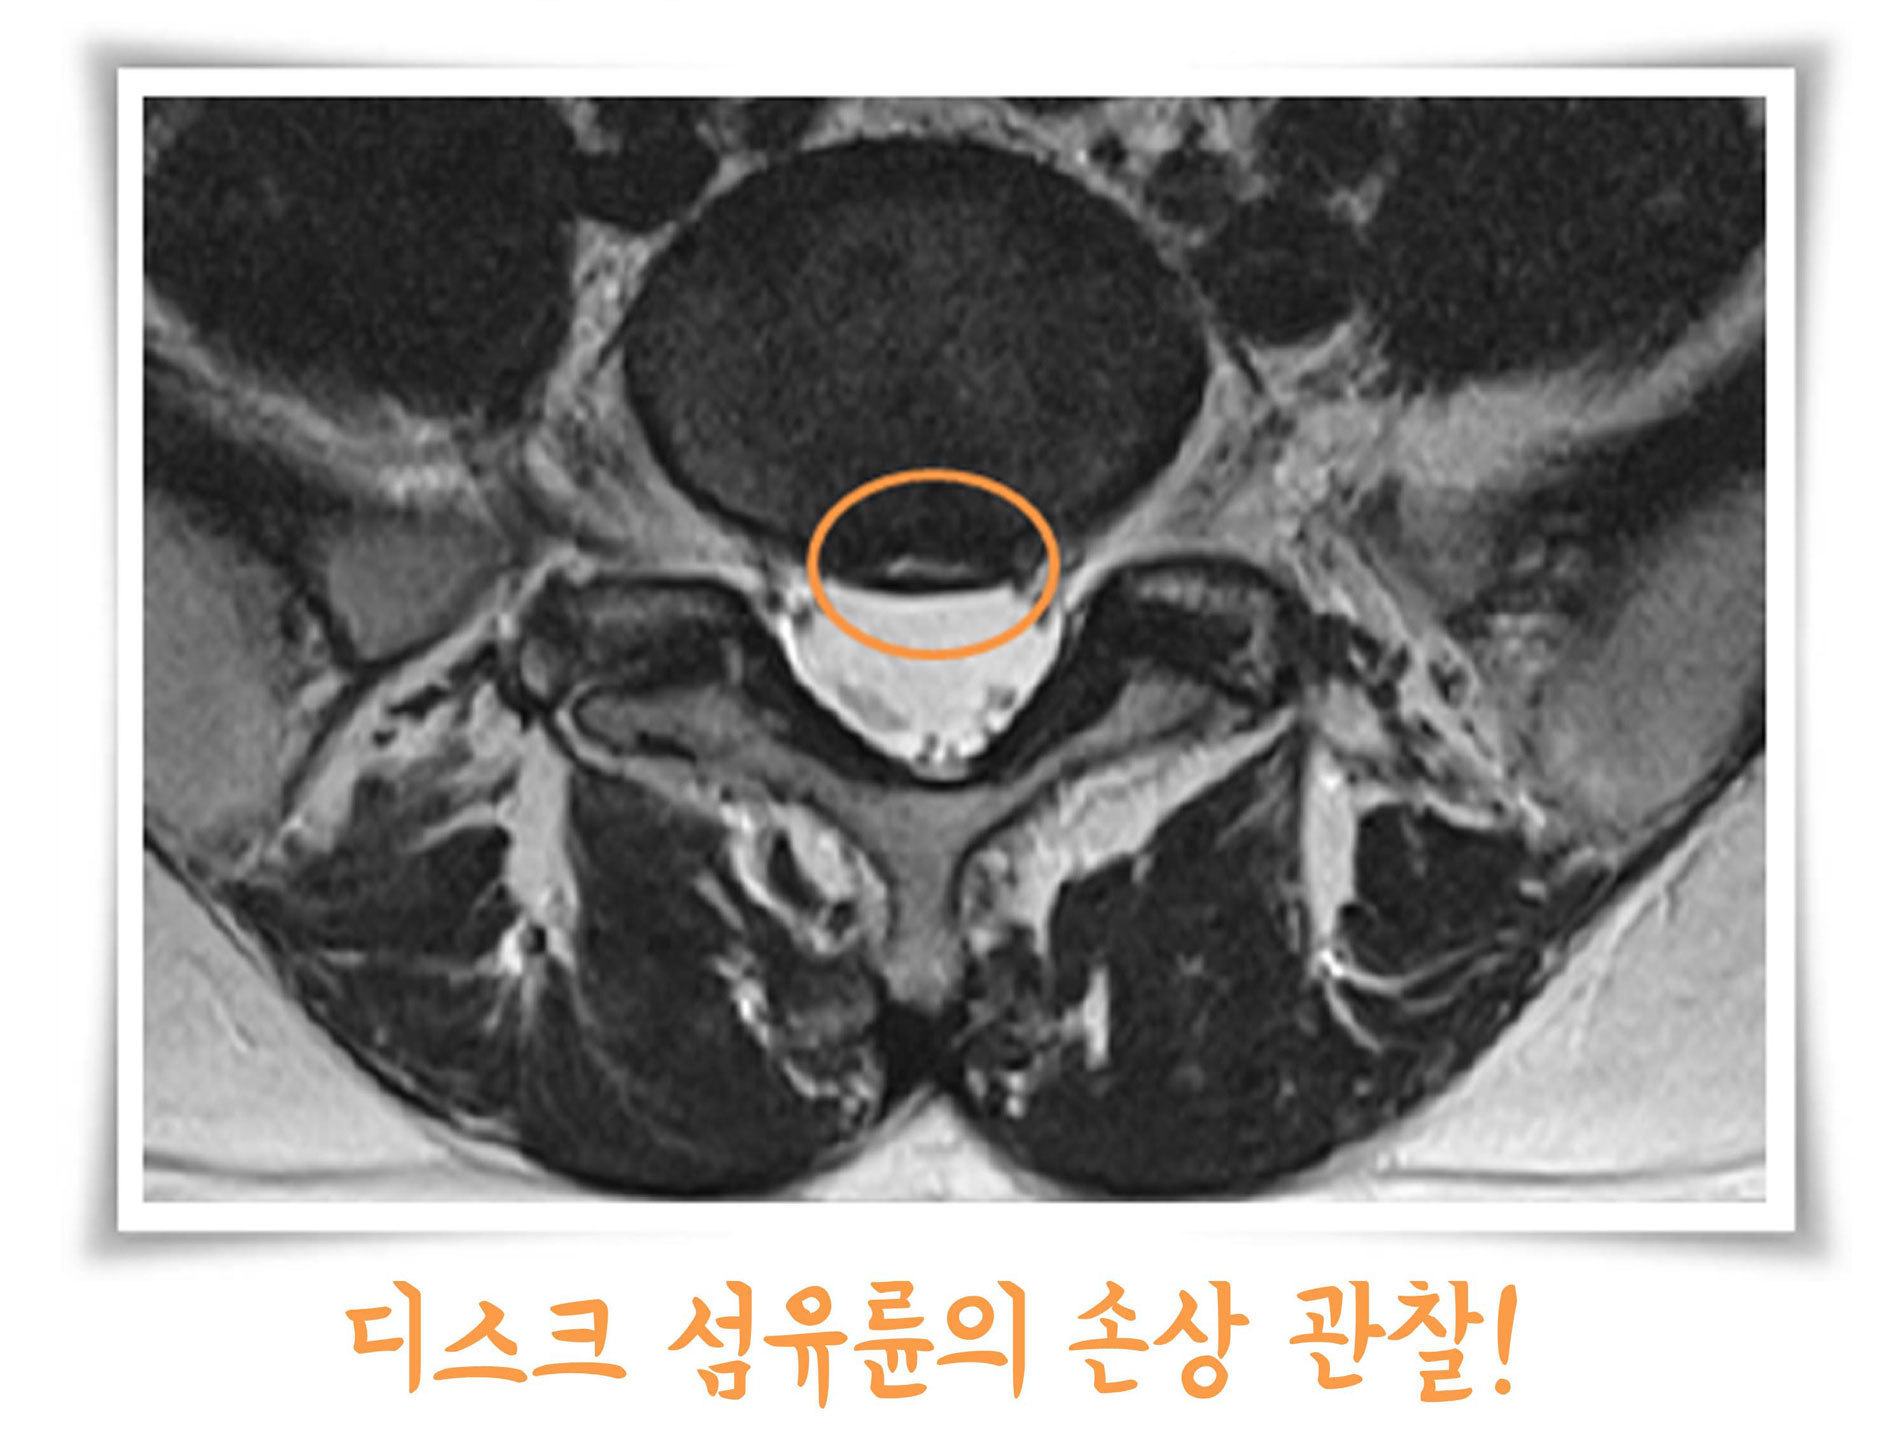

04. 추간판 내장증

추간판 섬유륜의 내부균열로 만성 요통과 하지의 방사통을 나타냅니다. 오래 앉아 있거나 앞으로 구부릴 경우 더 심해지며 엉덩방아, 교통사고 등 외상력이 있을 때 더 잘 발생합니다.

경막외 신경주사나 추간판 내로의 선택적 주입을 통하여 치료할 수 있습니다.